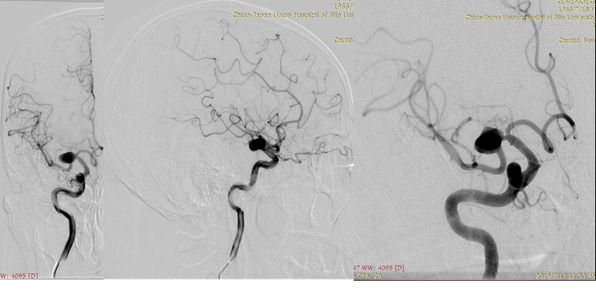

2、术后18小时急诊DSA(图六)。

图六

DSA术前后对比(图七)。

图七